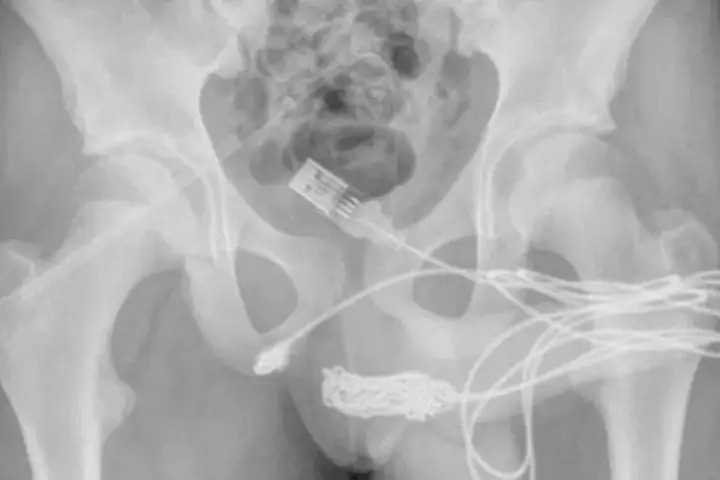

Após alguns Raio-X os médicos constataram que o fio havia dado um nó dentro do corpo do rapaz e só poderia ser removido cirurgicamente, através de uma incisão entre o pênis e o ânus do adolescente.

Segundo relatado ao Daily Mail, os médicos puxaram a extremidade do cabo, cortando-o do resto do fio antes de remover os pedaços restantes.